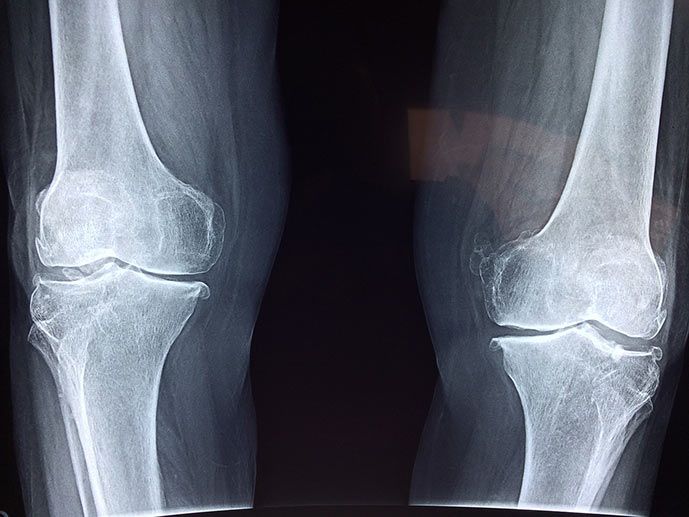

Rarefazione del tessuto osseo conosciuta come Osteoporosi

L’osteoporosi è una rarefazione del tessuto osseo che comporta una minore resistenza dell’osso e un maggior rischio di frattura.

Dal punto di vista fisiopatologico comporta una diminuzione della densità e della qualità ossea.